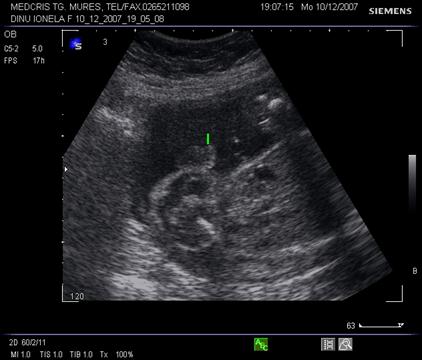

Fig nr. 190. Vezica urinara anecogena ( o sageata ) la nivelul pelvisului, in abdomenul superior , o alta formatiune anecogena , stomacul ( doua sageti ). Sarcina 16 sapt.